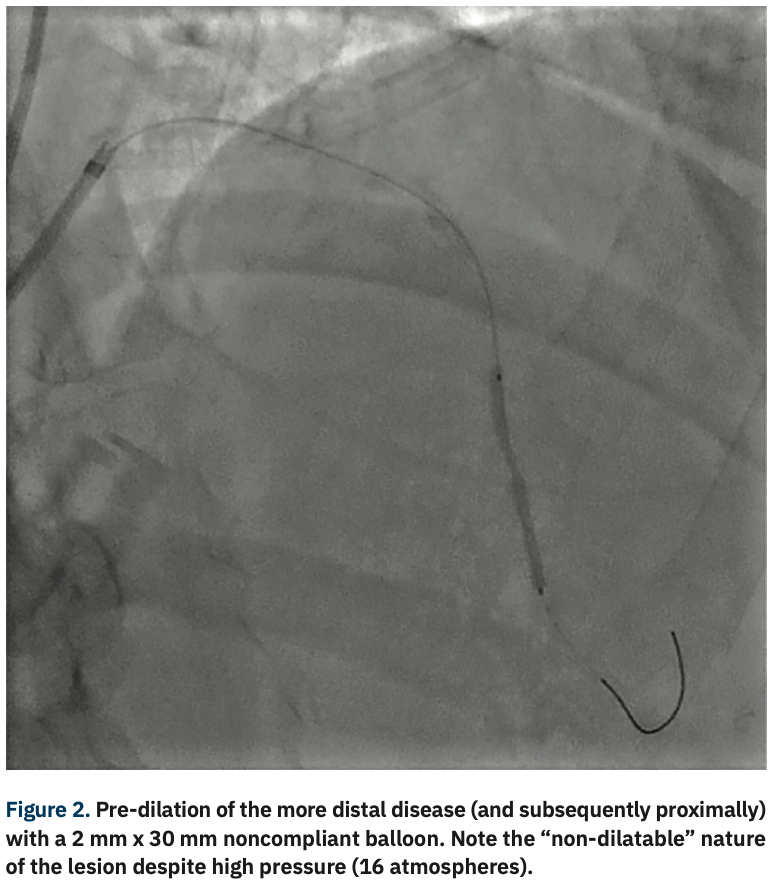

Like all centers, we are using more and more advanced imaging, but it is not uncommon for a lesion to be unpredictably difficult to dilate and more heavily calcified than is readily apparent on angiography. In those situations, with a lesion that will not dilate, it is necessary to have a method by which to modify the calcium, even though its presence was not anticipated. This is a particularly precarious situation for operators in non-backup settings. In the past, we would use oversized, non-compliant balloons and take them to very high pressures trying to achieve an adequate final stent result. In exceptionally rare cases, a handful of times over my 10 years here, we would even abort the case mid angioplasty and have to transfer the patient in a less than entirely stable fashion to the high-risk center. Calcium was our Achilles’ heel. We could always filter out the obviously high-risk cases, but there will always be a very small fraction of cases that do not have readily apparent calcium and are non-dilatable. IVL, from a safety standpoint, has been a game-changer for us not only in these cases, but also for cases with readily apparent calcium that otherwise would have required atherectomy. With the use of IVL, we are now at a point where the only cases that we have to either transfer or stage are non-crossable lesions: cases where you can get a wire but not a balloon across, and these are fairly rare.

While the extent of calcium might not be apparent on angiography, if you do see calcium, what happens next?

With the ability to more aggressively treat calcium here at our primary site with IVL, there has been a big uptick in our utilization of intervascular imaging such as intravascular ultrasound (IVUS). We are bringing in optical coherence tomography (OCT), with the idea that we will image a much higher fraction of our cases, because of this concept of unappreciated calcification. When we see either moderate or worse calcium, or have a recalcitrant lesion or lesion that is not dilating normally, we are quick to pull the IVUS imaging catheter out in order to assess the arc, length, and width of the calcium. Post IVL, we will generally reassess the lesion to confirm fracture of the calcium. We don’t require IVUS post IVL for stenting, but it definitely is something that makes us feel good about moving forward with stent implantation. More and more, intravascular imaging is going to be a marketable quality indicator. If you are only doing a small percentage of intravascular imaging, I think you are going to be perceived as a lesser quality program. There has been a longstanding resistance to adopting a higher utilization of intravascular imaging, because of the combination of cost and time. I wish that CMS would see the benefit and create a situation where there are not negative financial incentives to doing imaging.

Yes. IVL turns a difficult PCI into an easy PCI with a device that’s easy to use and financially viable for the hospital. The safety issue can’t be overemphasized. Cases that previously required the use of buddy wires, and secondary and tertiary balloons, add time and complexity. Balloon ruptures are also more frequent. You then have to use new balloons and the chance of having a complication such as a perforation goes up. All it takes is one perforation where you have to do a pericardiocentesis and salvage an emergency situation to see the value proposition of IVL. The cost of ambulance transfers and the cost of all the additional ancillary staff for a secondary procedure is also immense. Optimal procedural results also reduce readmission rates, which brings cost savings and quality improvement in terms of outcomes. IVL is a win across the board, for patients, providers, and administration.